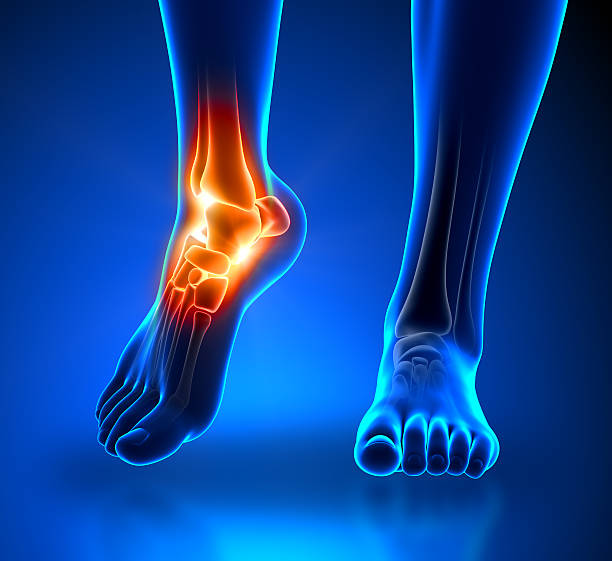

발뒤꿈치 통증의 원인 첫 번째는 족저근막염입니다. 족저근막은 발뒤꿈치 뼈에서 시작하여 발 앞쪽으로 내려가는 두껍고 강한 섬유질 밴드입니다. 족저근막은 우리 몸에서 중요한 역할을 하며, 아치형의 모양은 우리의 체중을 흡수하여 보행에 중요한 역할을 할 수 있습니다. 족저근막염은 족저근막에 반복적인 충격이 가해져 족저근막을 둘러싼 콜라겐이 퇴화되고 염증이 생기는 질환입니다.

증상은 원래 평발이거나 보행이나 생활 습관으로 인해 변형된 발, 구조적 이상이 문제가 될 수 있지만 기본적으로 하체를 과도하게 사용하면 문제가 생깁니다. 족저근막염의 통증은 사람마다 다르지만 기본적으로 발뒤꿈치, 특히 아침에 일어나 첫 걸음부터 통증을 느낄 수 있기 때문에 조기치료가 중요합니다.